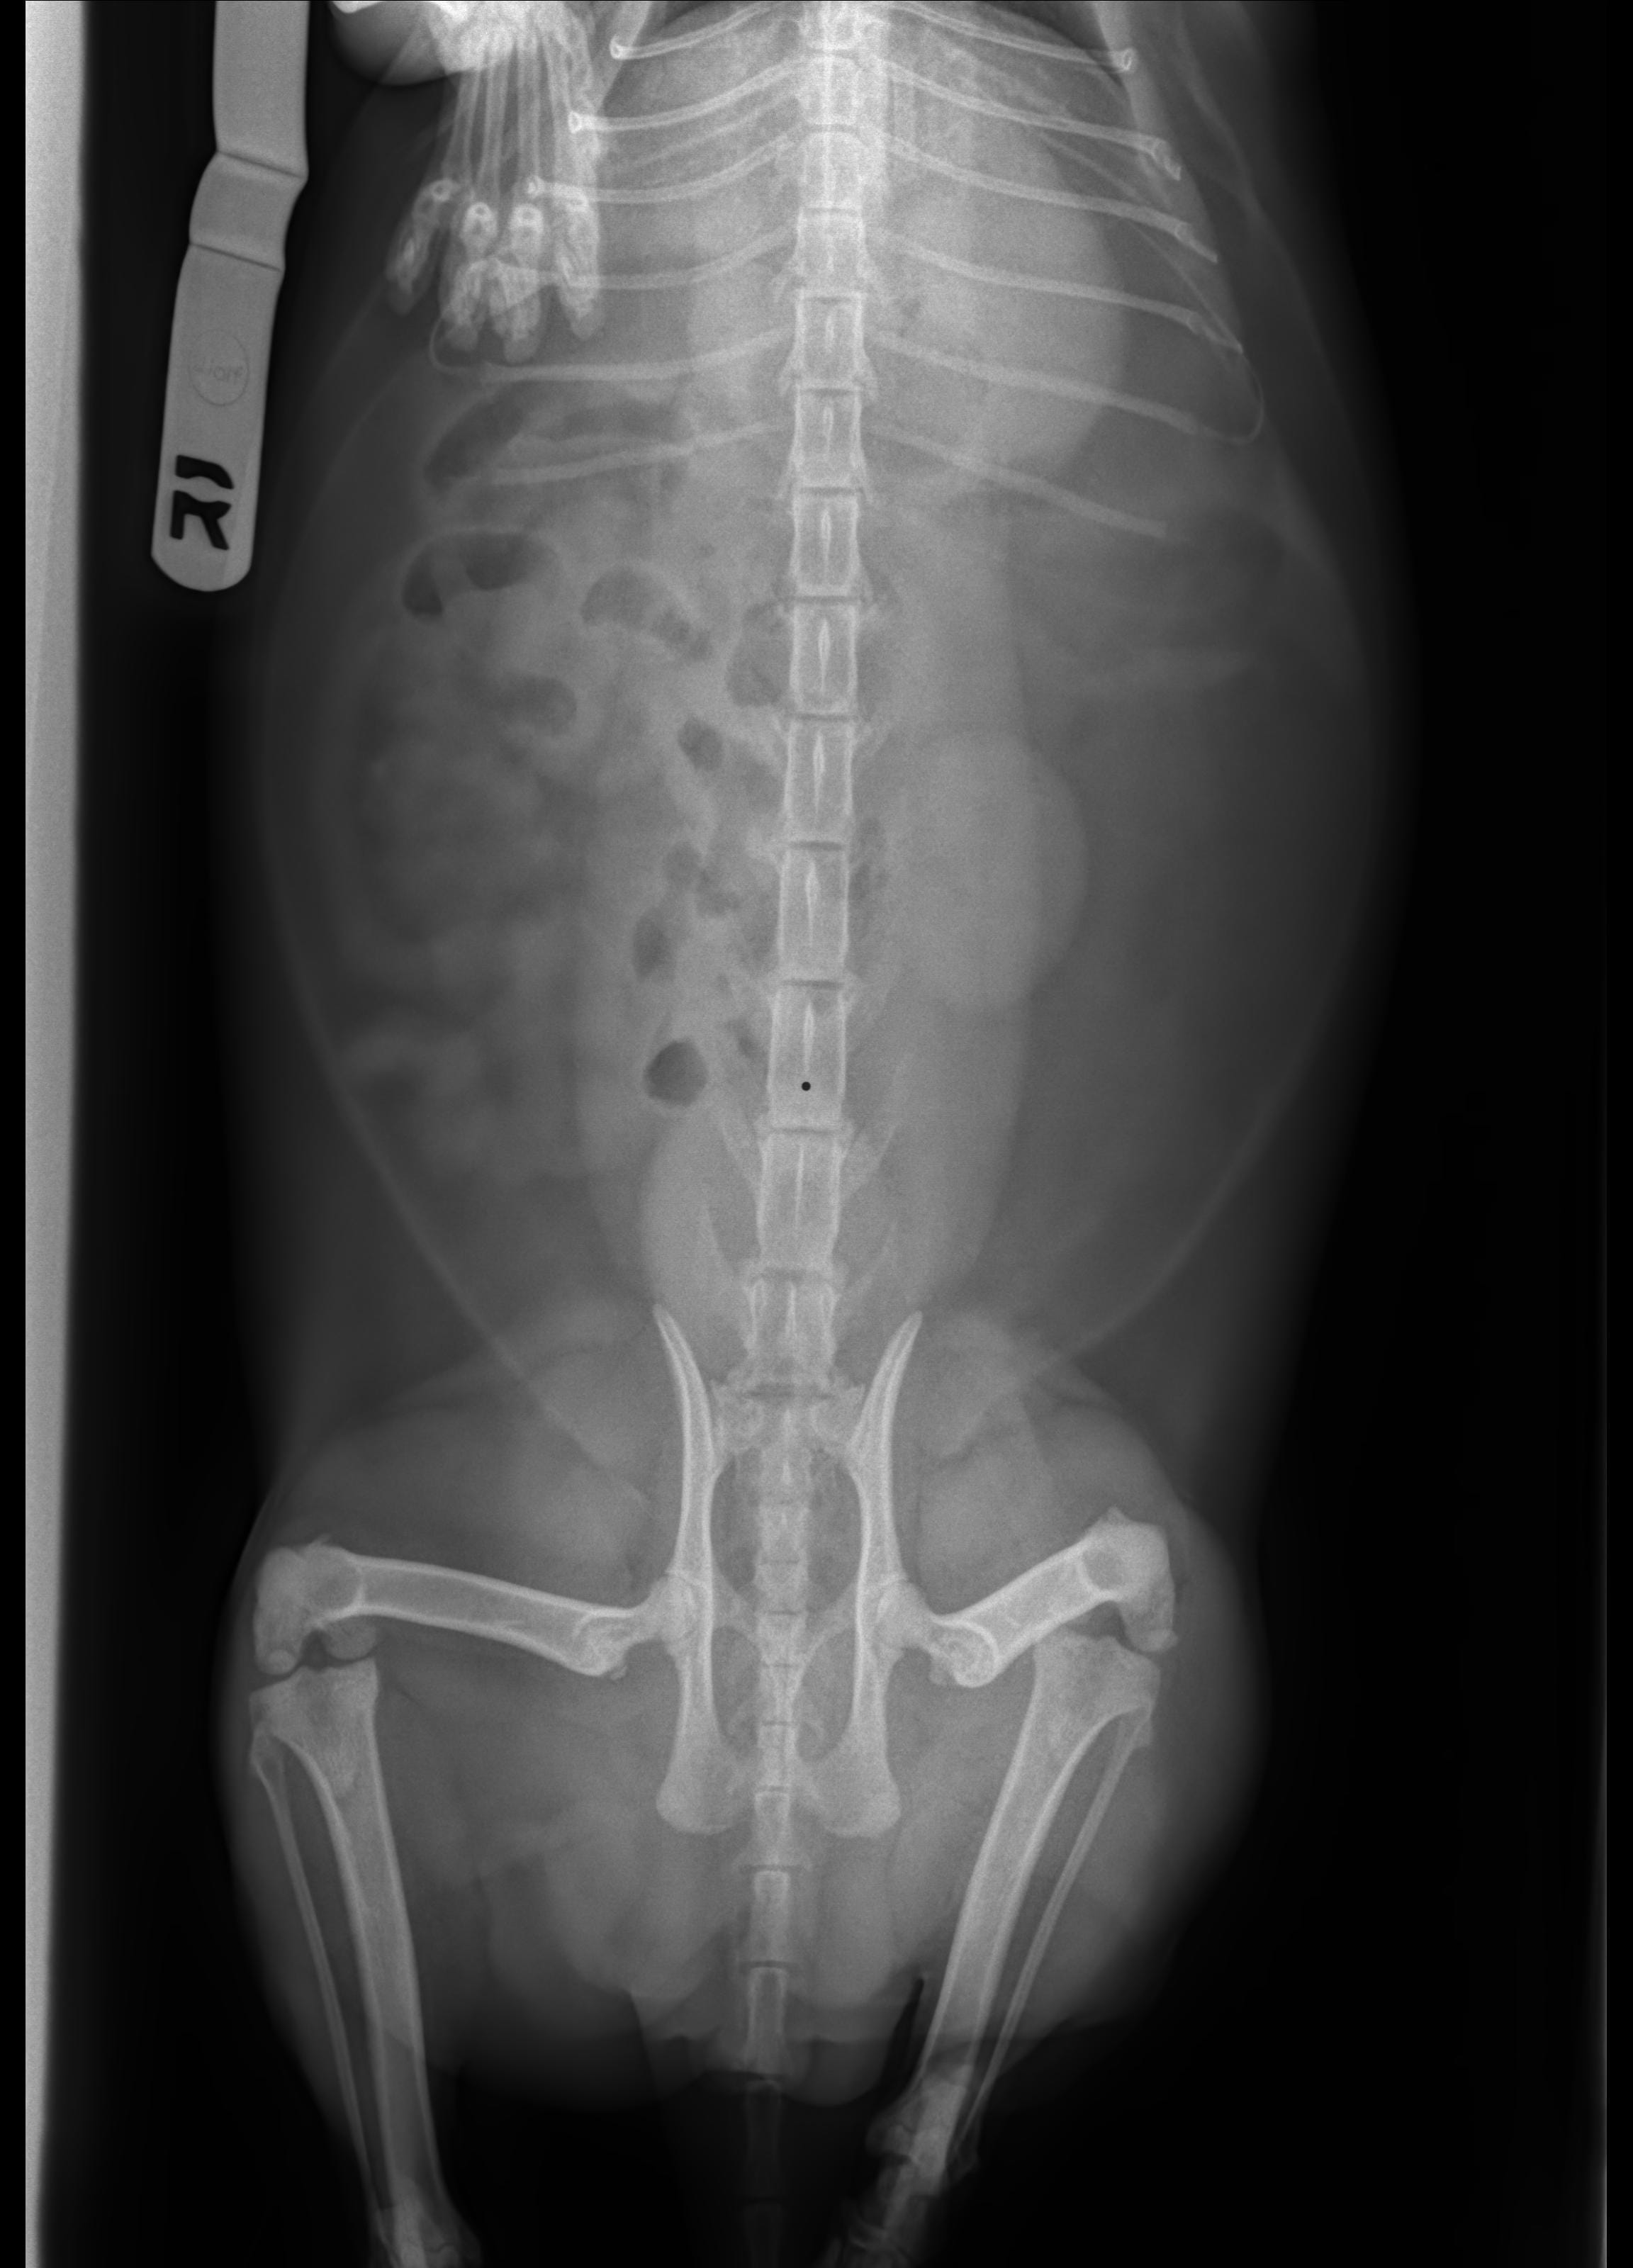

Hi, my cat is considered having a foreign body inside his abdomen. On the 1st day, he vomited alot so I took him to vet and after medication he stop vomiting but still acted abnormal. He has been losing his appetide 4 days, and he doesnt want to drink either. I dont see he urinates or defecates by himseft, so I try to help him by using enema to push all the poop inside him out and squeezing his bladder to help urinate. Now is 4th day, he drools constantly and I dont know what to do. Please help

I'm sorry to hear that Bo is feeling so poorly. A foreign body intestinal and/or stomach obstruction will cause vomiting and nausea (drooling is a sign of nausea), a loss of appetite and lethargy. Foreign body obstructions require surgery and supportive fluids and medications for treatment. Without surgical removal of the foreign material, the intestinal wall will become severely diseased and perforate, causing intestinal contents to leak into the abdomen, causing severe infection (sepsis) which is life-threatening. Since Bo is doing so poorly, I strongly recommend taking him to the emergency vet immediately for evaluation and likely surgery. Do not give additional enemas or squeeze his bladder without direct veterinary guidance. Some over the counter enemas (such as Fleet enemas) are toxic for cats. Squeezing his bladder could also cause an intestinal perforation if the intestines are diseased from the foreign material. I hope that all goes well.